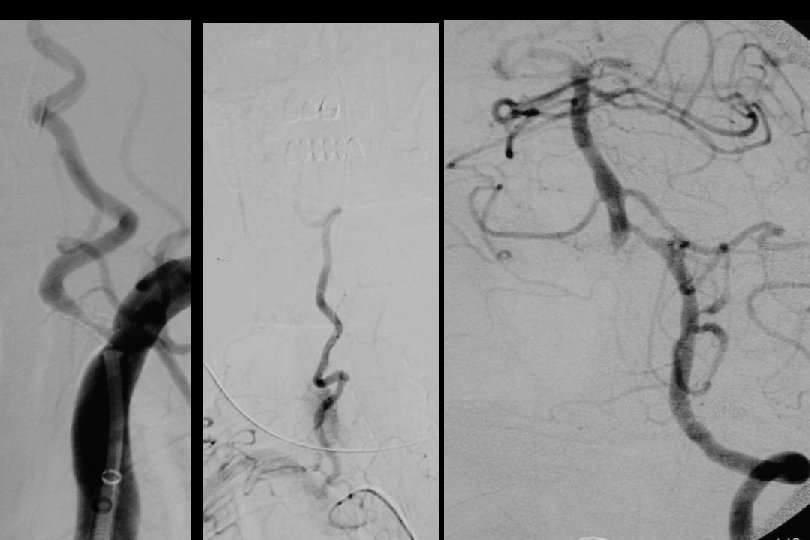

71 y kadın hasta En iyi medikal tedavi altında post fossa iskemik ataklara neden olan baziler stenoz

Sağ brakial yaklaşım ile Reflex /Navien servikal R- VA’e ve intrakraniyal segmente ilerletilmiştir.

PTA sonrası

. . 6 mm Solitaire ile Stentleme sonrası